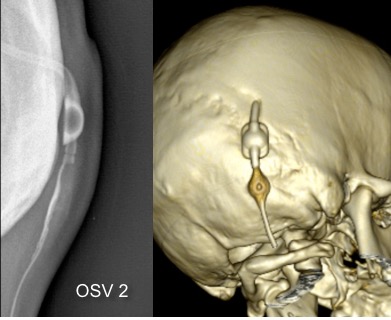

il existe un grand nombre de valves ; il n’est pas toujours aisé de les reconnaitre radiologiquement. voici la liste des plus courantes :

comment reconnaitre radiologiquement le type de valve ?